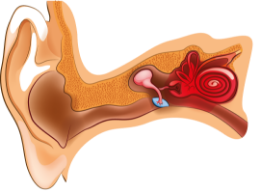

Отит – запальне захворювання одного з відділів вуха.

Існують різноманітні види отиту в залежності від того, яка частина вуха запалена або інфікована.

Зовнішній отит

Середній отит

Середній отит - це запальне захворювання середнього вуха, пов'язане з потраплянням в нього інфекції.

Внутрішній отит (Лабіринтит)

Лабіринтит - це запалення внутрішнього вуха. Лабіринтит з усіх різновидів отитів становить найбільшу небезпеку. При запаленні внутрішнього вуха типові симптоми включають порушення слуху, вестибулярні порушення - запаморочення, втрату рівноваги і орієнтації в просторі. Лікування внутрішнього отиту проводиться під наглядом лікаря з урахуванням етіології і патогенезу захворювання.